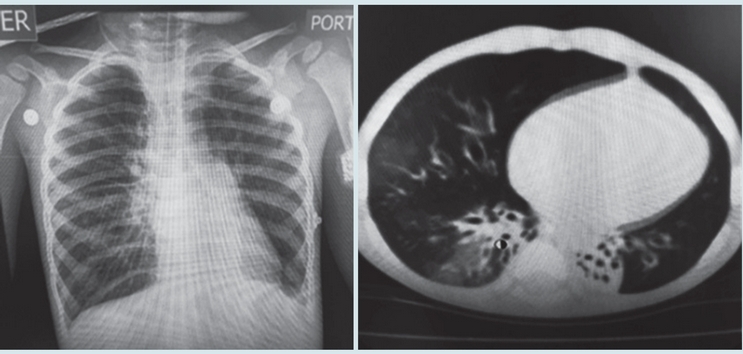

TACAR de bronquiectasias

A

How well did you know this?